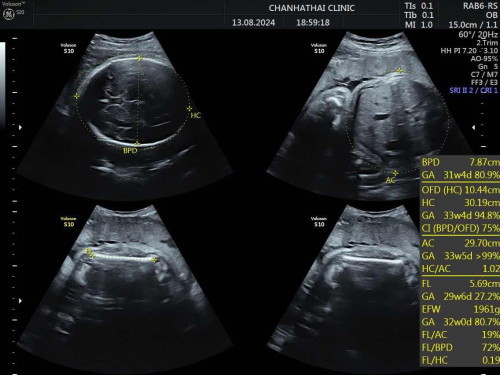

อันตร้าซาวด์ตอนอายุครรภ์ 30+1 น้ำหนัก 1961 กรัม ถือว่าปกติตามเกณฑ์ไหมคะ พอดีวันนั้นลืมถามคุณหมอ 😅